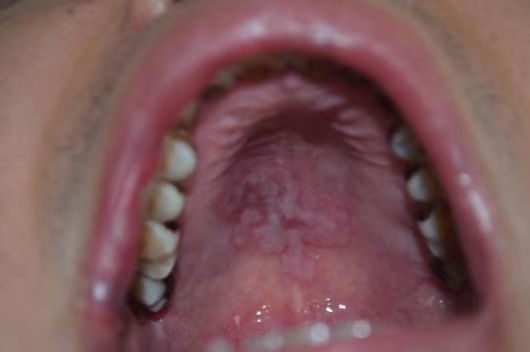

梅毒患者口腔

HIV患者毛状白斑伴真菌感染

若在诊疗前,患者传染病结果为阳性,临床医生会安排单独的诊室为患者诊疗,在诊疗结束后,会根据传染病的传播途径,科学、及时的对物体表面和空气进行终末消毒,严格落实消毒隔离管控,以避免医护人员、其他患者及患者家属的感染风险,为就诊患者提供安全可靠的就医环境。